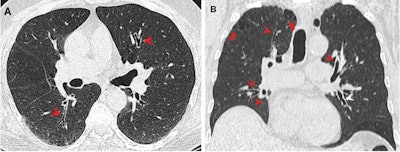

CT images show airway changes in a 66-year-old male marijuana and tobacco smoker. Contrast-enhanced (A) axial and (B) coronal images show cylindrical bronchiectasis and bronchial wall thickening (arrowheads) in multiple lung lobes bilaterally in a background of paraseptal (arrows) and centrilobular emphysema. Images courtesy of RSNA.Murtha and colleagues included a total of 146 people in their study. Out of these, 56 were marijuana smokers with an average age of 49 years, 57 were nonsmokers with an average age of 49 years, and the remaining 33 were tobacco-only smokers with an average age of 60 years.